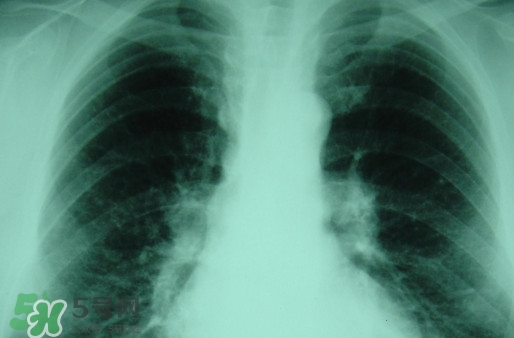

塵肺病多半是因?yàn)榉尾课牖覊m導(dǎo)致呼吸不順暢,引發(fā)細(xì)菌感染的病癥,而且隨著近年來(lái)塵肺病人得增多及死亡率,國(guó)家對(duì)此發(fā)布了相關(guān)政策。那么,塵肺病吃什么藥能清肺?塵肺病國(guó)家有什么政策?

很多人不知道,其實(shí)塵肺病分為無(wú)機(jī)塵肺和有機(jī)塵肺兩種?;颊哂捎谠谌粘5墓ぷ髦兄虚L(zhǎng)期吸入生產(chǎn)性粉塵(灰塵),這些粉塵在肺內(nèi)滯留,從而引起的了塵肺病這種全身性疾病,很多人對(duì)此認(rèn)識(shí)并不清楚。

吸入無(wú)機(jī)粉塵所致的塵肺,稱為無(wú)機(jī)塵肺;吸入有機(jī)粉塵以后患病被稱為有機(jī)塵肺。對(duì)早期矽肺療效較好的藥物可以選擇克矽平,有阻止和延緩矽肺進(jìn)展的作用。同時(shí)也肯那個(gè)會(huì)出現(xiàn)發(fā)癢、硬塊,肌肉跳動(dòng)等不良反應(yīng)。